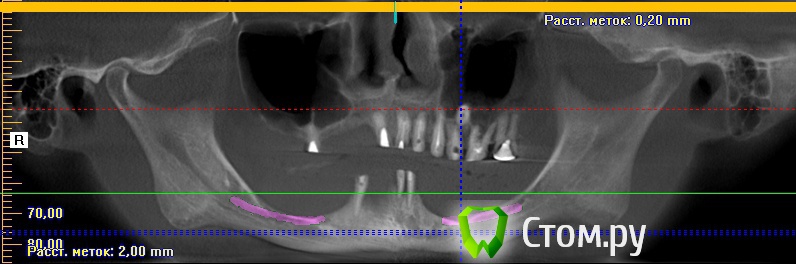

Игорь Пеликан Опубликовано 19 января, 2014 Поделиться Опубликовано 19 января, 2014 Прошу поделиться своими мыслями по поводу хирургической реабилитации(костная пластика) девушки 35 лет,все это покрыто двумя сьемниками.Верх-2 сектор оставляем,в 1 секторе синус,3D.Низ-закапываются сомнения в васкуляризации графта в дистальных отделах, 3D или репозиция,не хочется воспользоваться только междументальным расстоянием? Ссылка на комментарий

Игорь Пеликан Опубликовано 19 января, 2014 Автор Поделиться Опубликовано 19 января, 2014 Дистально костных пик нетзеленая линия на панорамнике проходит как раз таки по костным пикам,прирост все таки возможен? Ссылка на комментарий

АнтонТЛТ Опубликовано 19 января, 2014 Поделиться Опубликовано 19 января, 2014 (изменено) Дистально ветвь нижней челюсти, а не пики альвеолярного отростка. На такую высоту за один раз не поднять (если делать 3д) Изменено 19 января, 2014 пользователем АнтонТЛТ Ссылка на комментарий